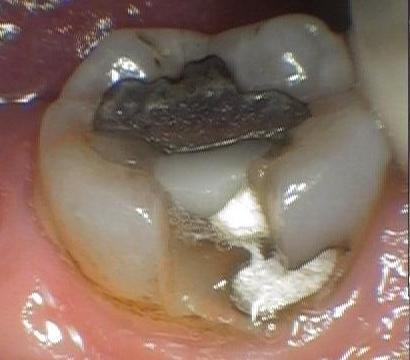

This patient came to us with a fractured tooth and a large existing metal filling. The tooth was also sensitive to cold. After removing all the old filling materials and smoothing, a tooth-colored composite filling was used to repair the tooth. The tooth should now function for years to come, and the temperature sensitivity greatly improved.